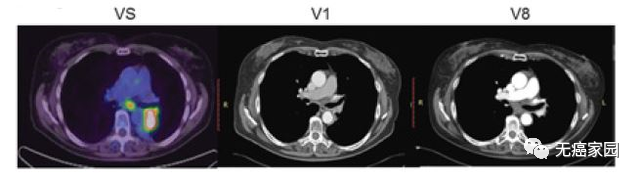

接下来,小编展示联合疗法中一个典型的成功案例,如图所示:治疗1~2个月后复查,肺部肿瘤完全消失,并且疗效已经保持了18个月。

本研究中,采用局部输注 NKG2Dp CAR-NK的方式治疗了3 例转移性结直肠癌患者。前两例患者腹腔输注低剂量 CAR-NK 细胞后,可观察看腹水生成量减慢以及腹水样本中肿瘤细胞的数量急剧减少。第三例肝转移瘤患者采用超声引导下瘤内经皮注射和腹腔内灌注方式输注 CAR-NK细胞后,多普勒超声可见肝部肿瘤快速缩小,正电子发射断层扫描(PET-CT)提示经治疗的肝病灶为完全代谢反应。3 例患者在治疗过程中均无出现3级或以上的不良事件。

第3例患者多普勒超声成像显示局部注射 CAR-NK 细胞降低肝转移病灶肿瘤负荷

CAR-NK 细胞治疗后肝转移病灶 PEC-CT 结果对比图

(患者肝Ⅵ段的最大氟脱氧葡萄糖(FDG)摄取值从 8.2 降至 0.14,经评估为完全代谢缓解)